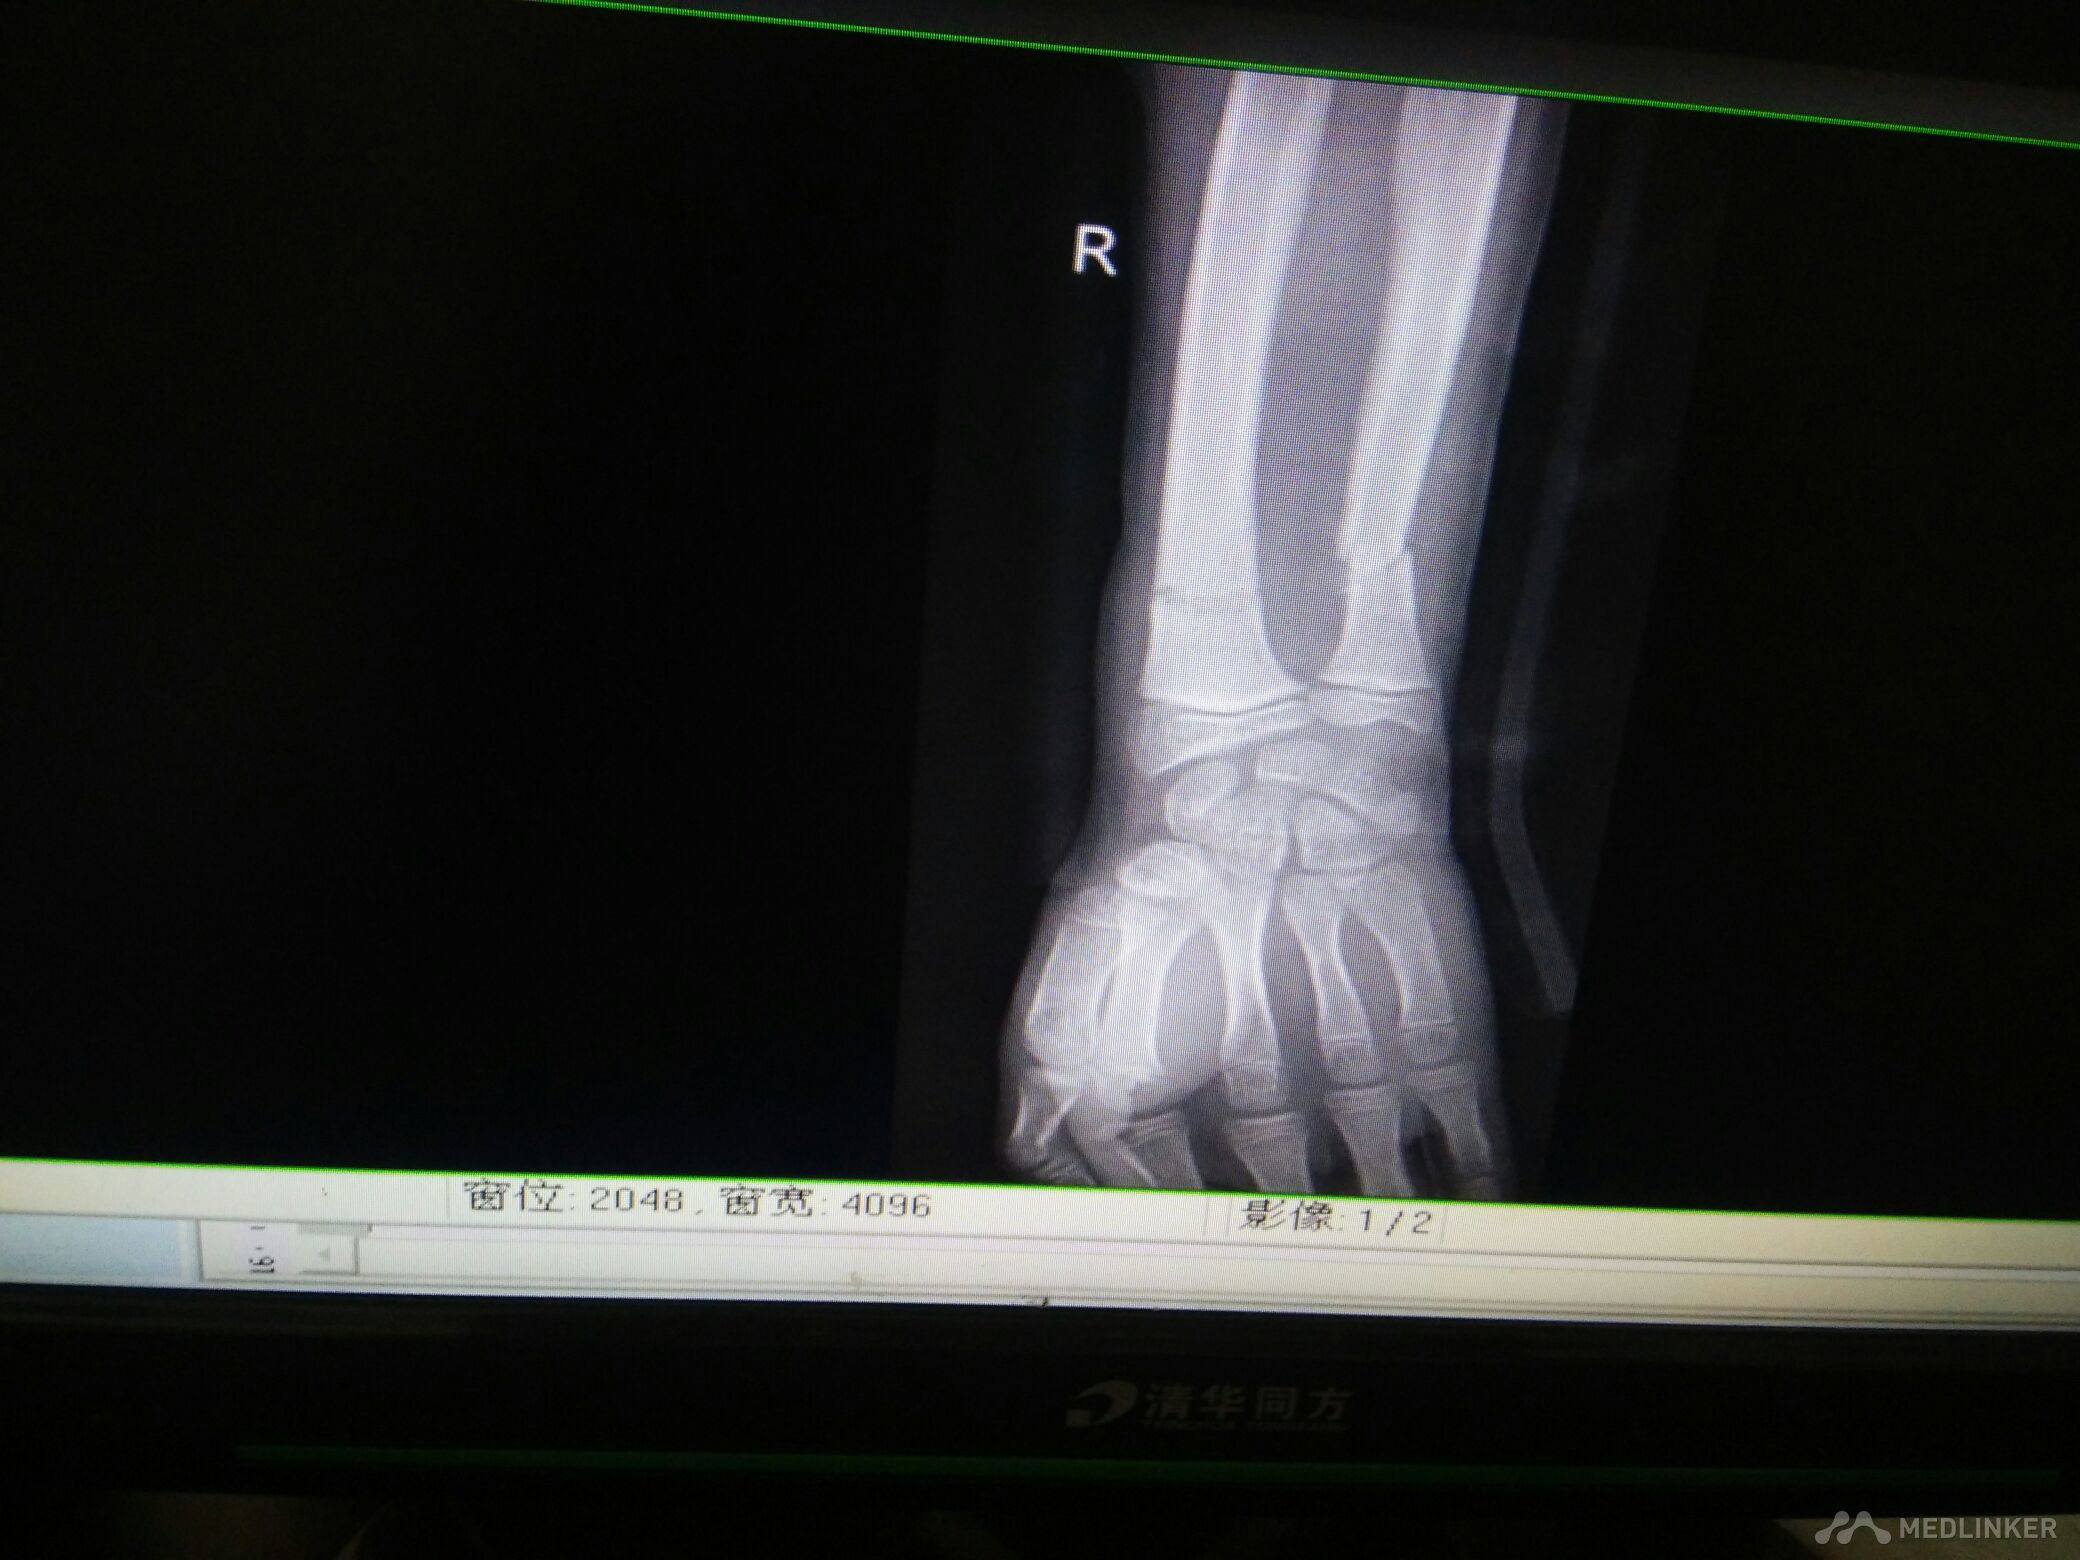

脾破裂,右尺桡骨骨折

尺桡骨骨折

病员男性,15岁。车祸伤致腹痛、右腕部畸形活动受限3小时入院,腹部B超提示:腹腔肠间隙积液,脾破裂。DR检查:右尺桡骨远端骨折。入院后行急诊剖腹探查术脾切除,右尺桡骨手法复位小夹板外固定,右腕复查对位久佳,这种还须手术切开复位吗?